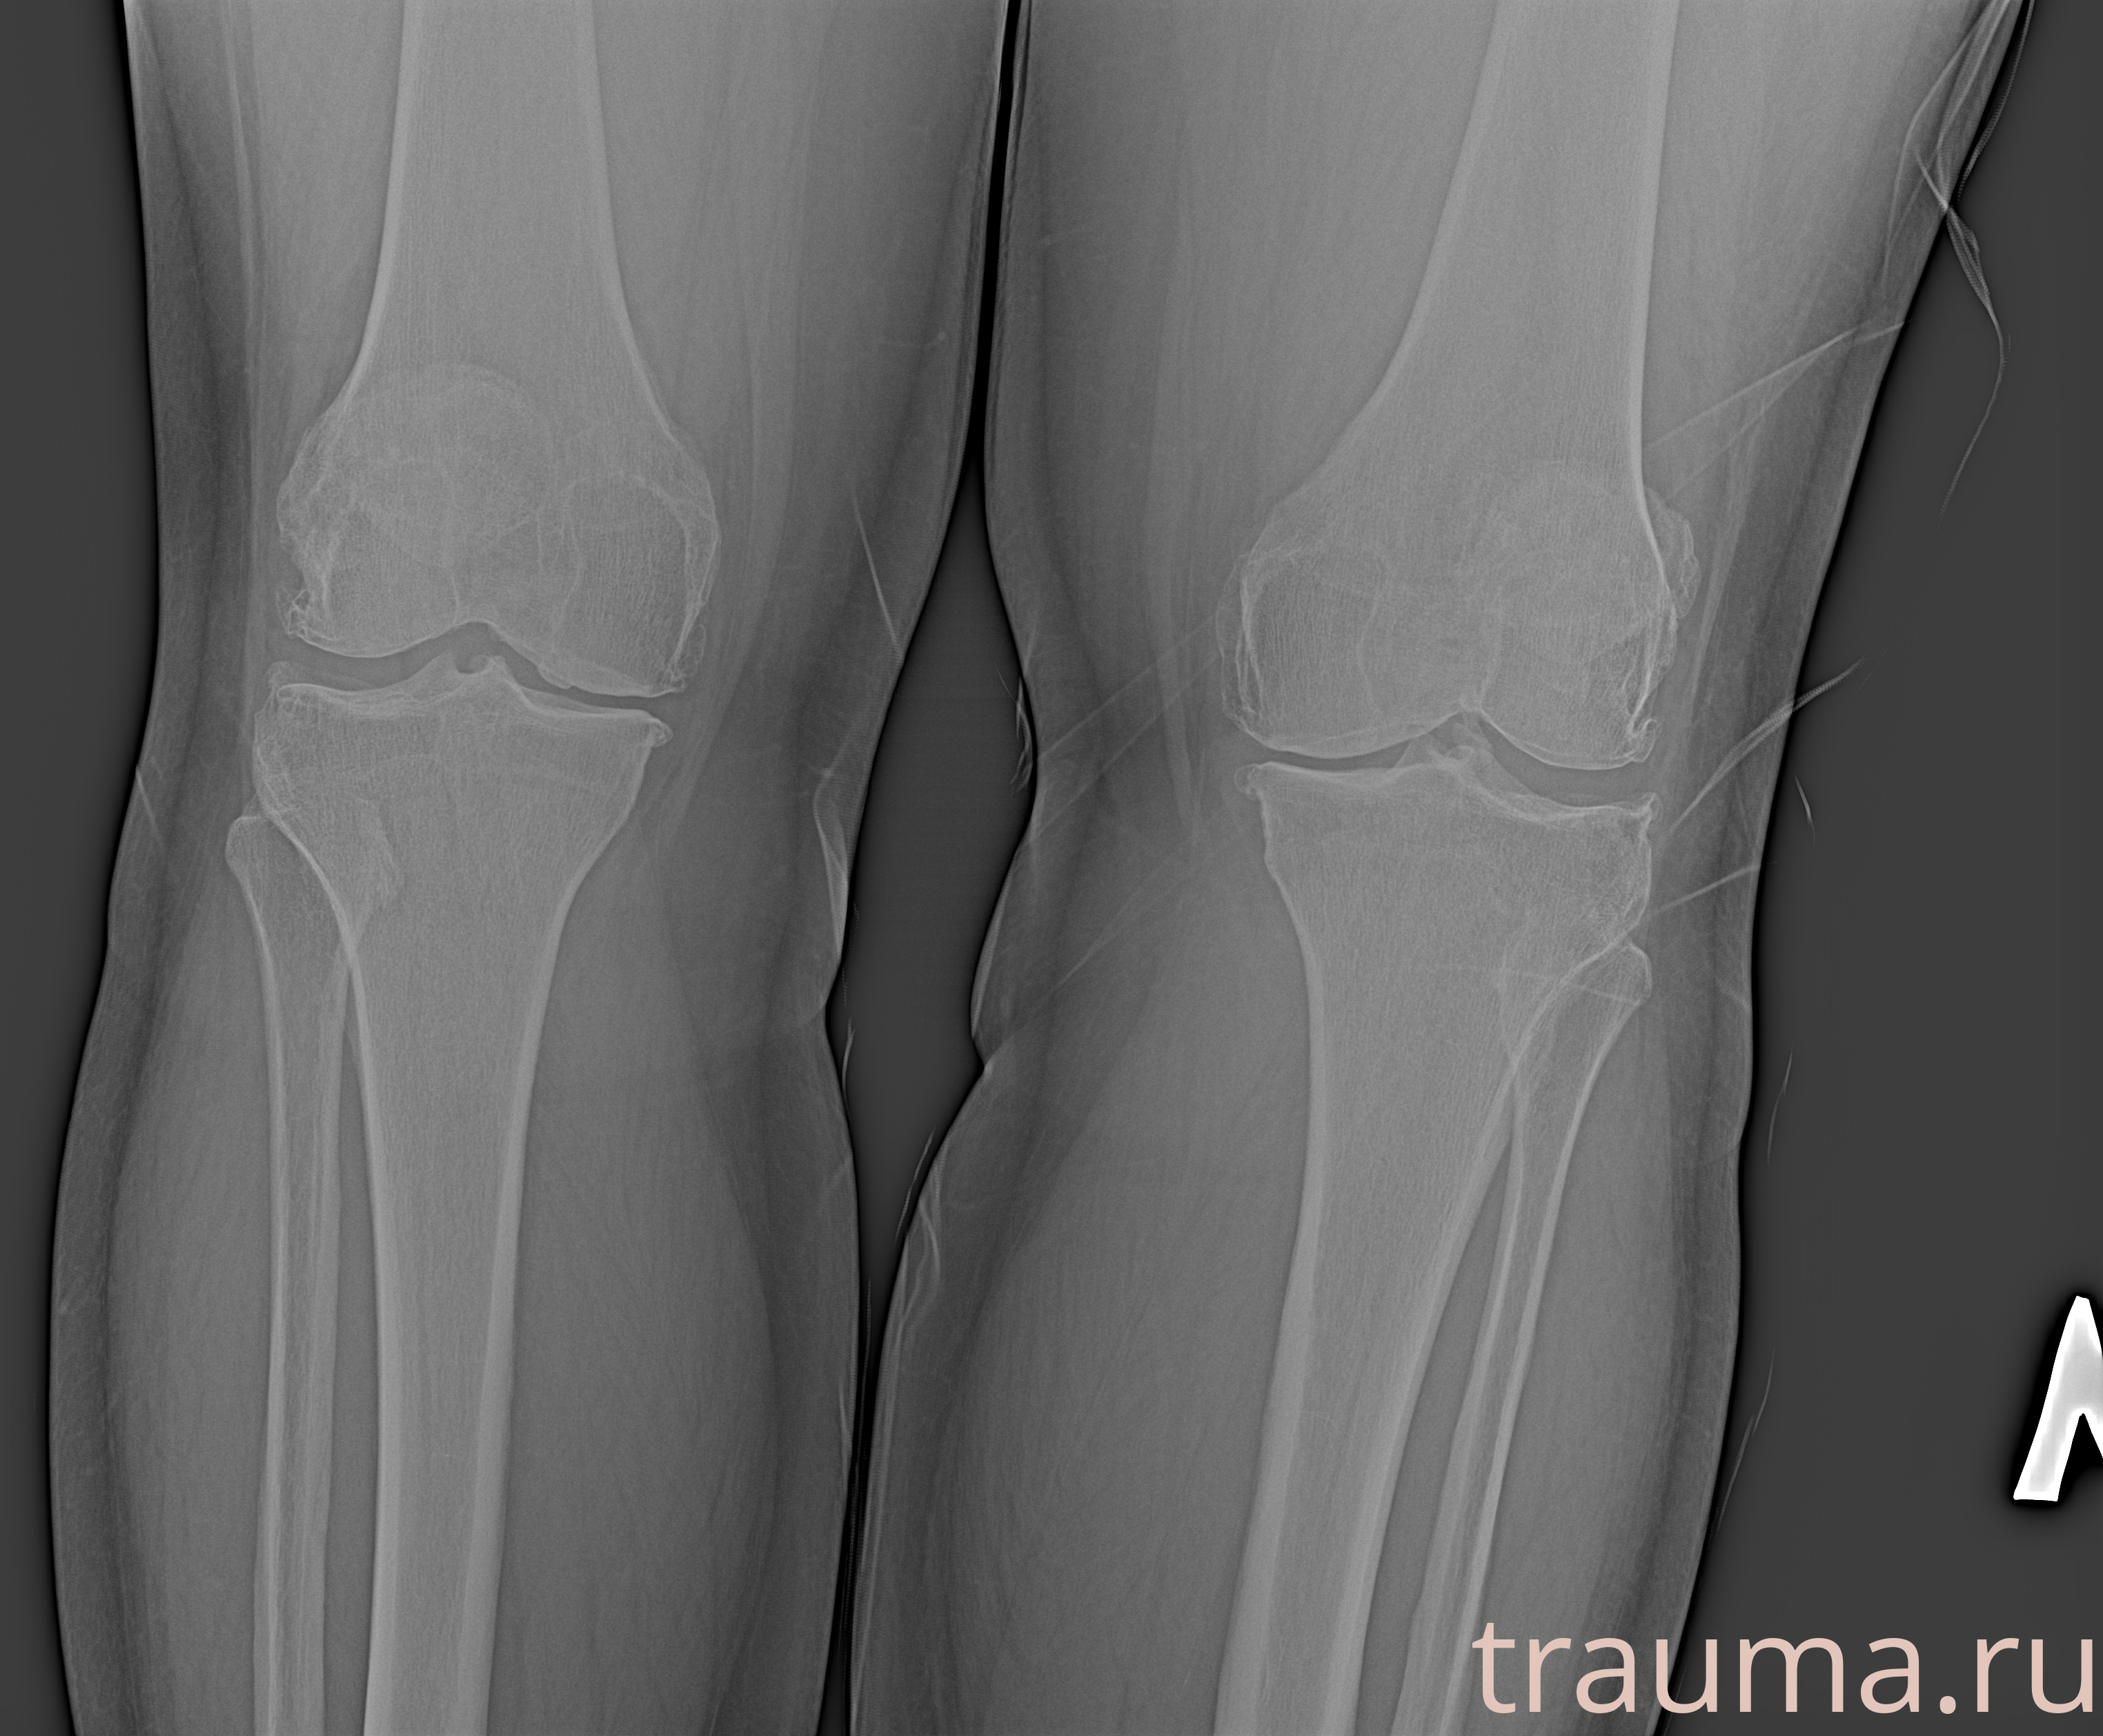

Рентген на дому: по вашему адресу приезжает врач-рентгенолог, травматолог-ортопед с мобильным рентгеновским аппаратом, проводит диагностику травмы или заболевания, делает необходимые рентгенограммы, дает рекомендации по дальнейшему лечению. Получить качественные снимки в домашних условиях возможно благодаря уникальной методике, разработанной МосРентген Центром для института  Склифосовского